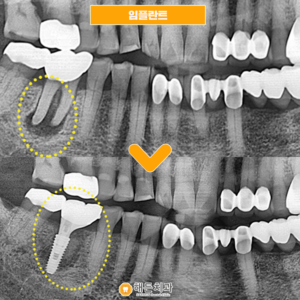

배방역치과 자연치아를 살리기 위해서는 (치료기간 : 2022.03~2022.06)   안녕하세요. 오늘은 저희 배방역치과를 내원하여 임플란트와 치관확장술을 통해 크라운치료하신 환자분을 소개해 드릴까 하는데요.   아래 사진을 보면서 설명해 드리도록 하겠습니다. 배방역치과 위 사진은 고*님의 치아 사진입니다. 고*님은 식사 때마다 통증을 느끼고 불편감을 느낀다고 하여 상담을 원한다고 하셔서 저희 치과에 내원해 주셨는데요,   더보기…